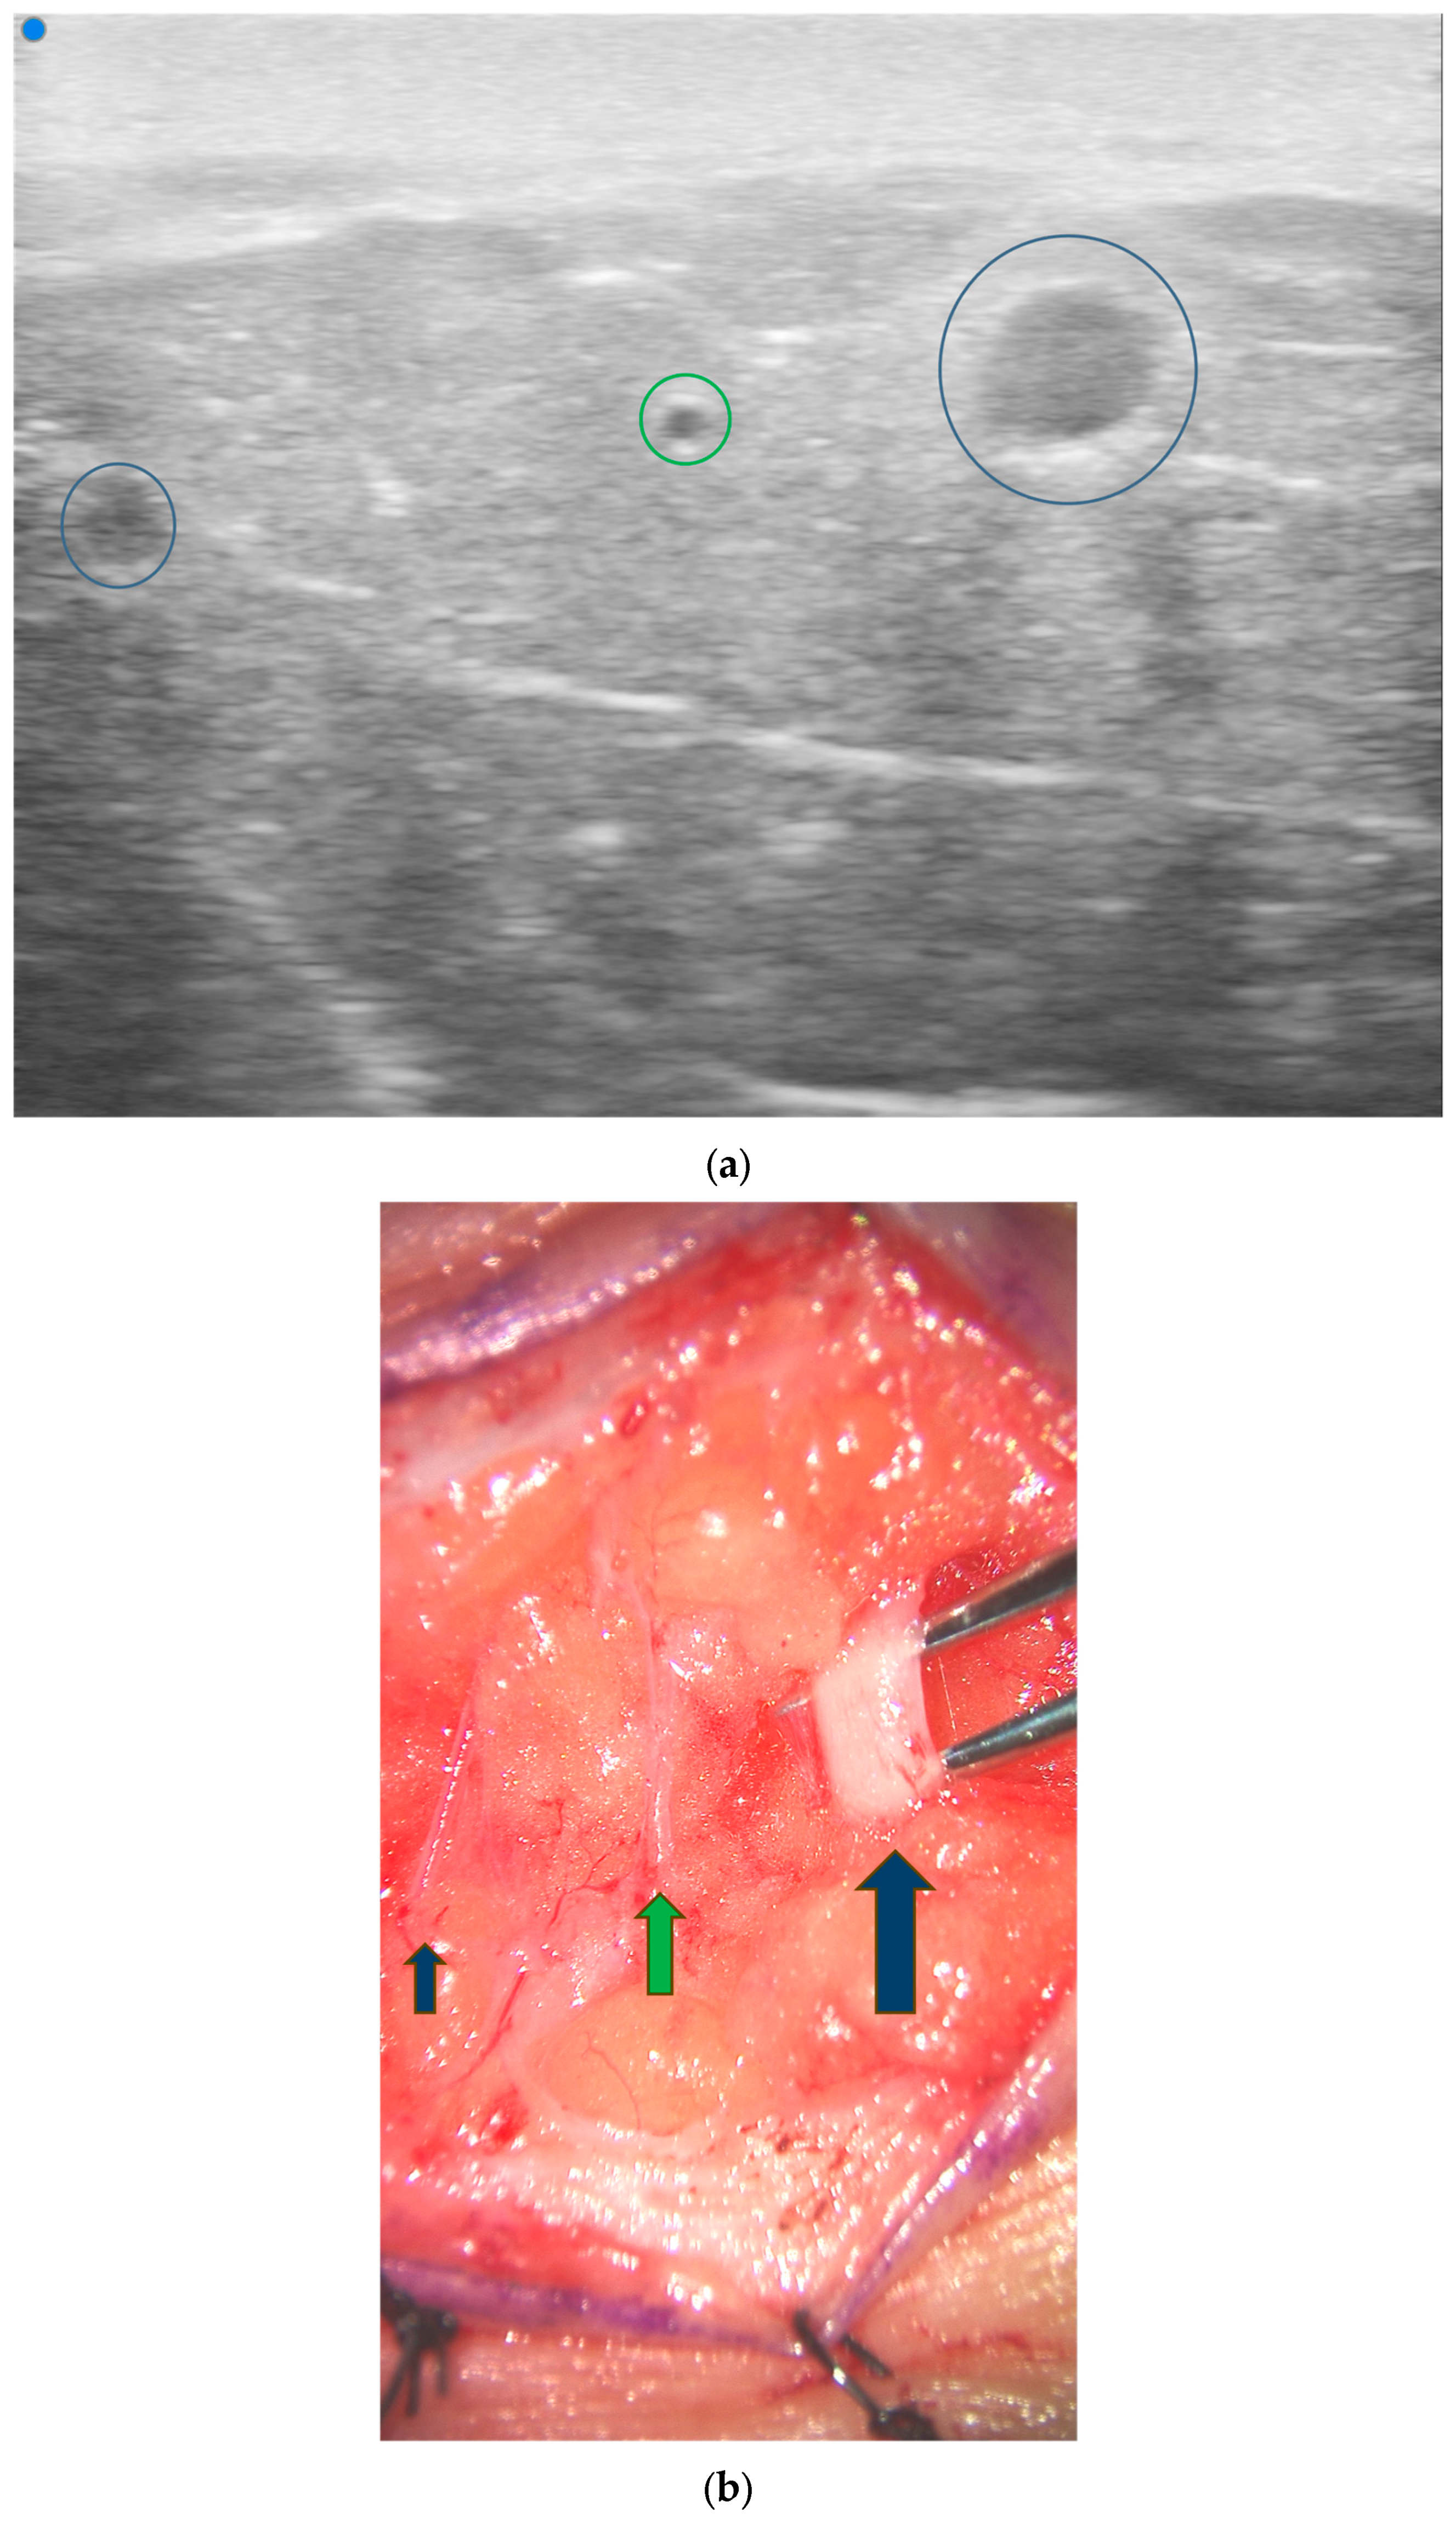

3.4. Lymphatic Surgery

- Hayashi, A.; Giacalone, G.; Yamamoto, T.; Belva, F.; Visconti, G.; Hayashi, N.; Handa, M.; Yoshimatsu, H.; Salgarello, M. Ultra High-frequency Ultrasonographic Imaging with 70 MHz Scanner for Visualization of the Lymphatic Vessels. Plast. Reconstr. Surg.-Glob. Open 2019, 7, e2086. [Google Scholar] [CrossRef] [PubMed]

- Hayashi, A.; Visconti, G.; Giacalone, G.; Hayashi, N.; Yoshimatsu, H. Recent Advances in Ultrasound Technology: Ultra-High Frequency Ultrasound for Reconstructive Supermicrosurgery. J. Reconstr. Microsurg. 2022, 38, 193–199. [Google Scholar] [CrossRef] [PubMed]

- Bianchi, A.; Visconti, G.; Hayashi, A.; Santoro, A.; Longo, V.; Salgarello, M. Ultra-High frequency ultrasound imaging of lymphatic channels correlates with their histological features: A step forward in lymphatic surgery. J. Plast. Reconstr. Aesthetic Surg. 2020, 73, 1622–1629. [Google Scholar] [CrossRef] [PubMed]